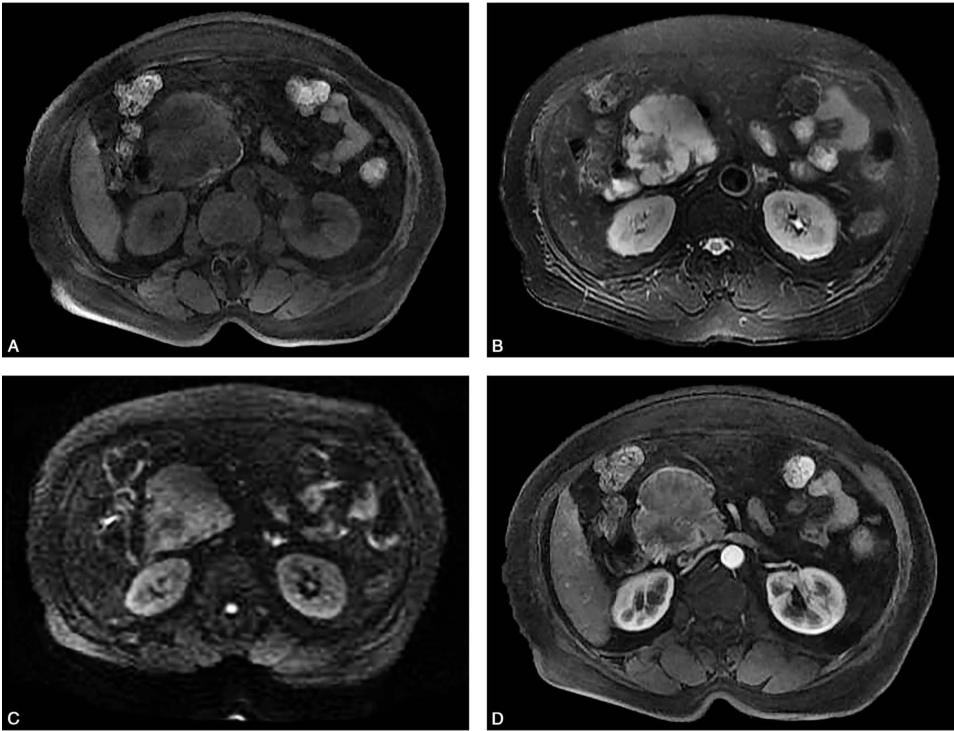

腹部超声(图3)显示胰头稍低回声团块,大小约5.2cm×5.9cm,边界尚清,形态欠规则,内部回声不均匀,似见分隔样回声,纵切面病灶呈大分叶状,内可见少许血流信号。与周边血管分界清。

图3 腹部超声

A.二维超声;B.腹部彩色超声。